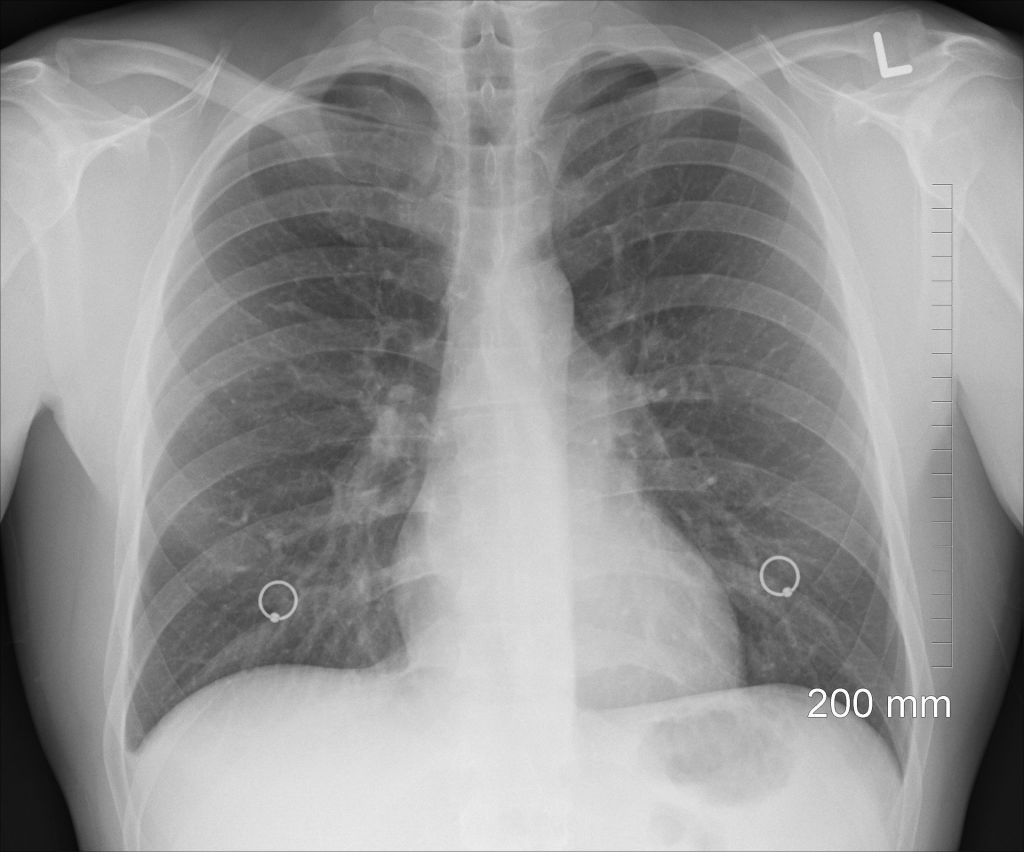

7Problemas respiratorios

Consumir paracetamol en exceso pueden producir efectos secundarios respiratorios, que incluyen la disnea o, en casos más graves, la neumonía eosinofílica.

Además, se ha probado que el abuso de paracetamol agrava los síntomas del asma. Un estudio recomienda reducir la dosis en personas asmáticas. El uso regular de paracetamol puede empeorar los síntomas del asma al reducir la presencia en la sangre del antioxidante glutation, un protector pulmonar natural.